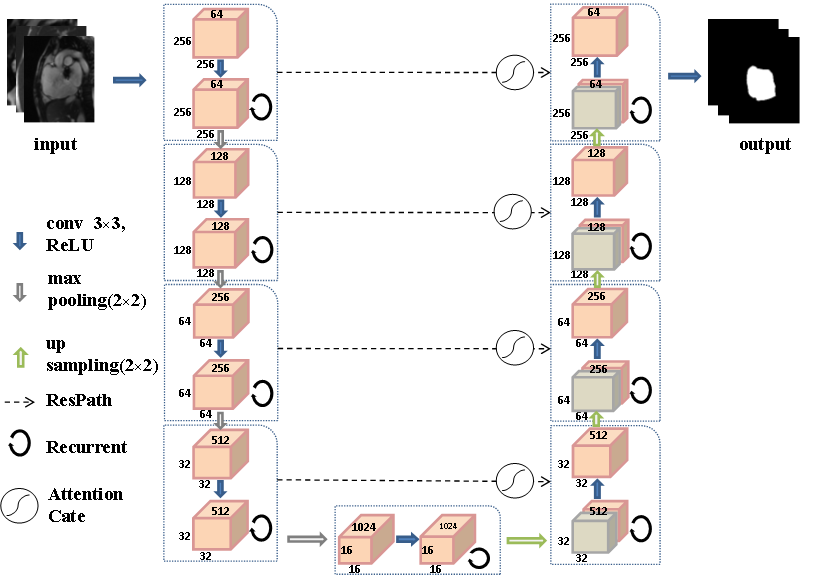

随着计算机计算能力的不断提高,卷积神经网络已在计算机视觉领域得到广泛应用,并取得了突破。建立了一个受U-Net启发的完全卷积网络,以实现医学图像的端到端目标和背景分类。

图8 所提出的RA-UNet网络体系结构